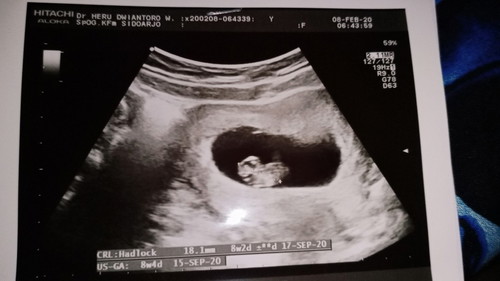

Assalamualaikum wr.wb bund.ini waktu periksa 8minggu. Sekarang mungkin masih 9minggu 6hari . Mau tanya bunda kalo hamil di usia ini kok badan semakin lemas ya dan selalu pusing dan mual kadang perut kayak kram gitu bund.apa karna kurang vitamin atau gimna bund .terus usia kandungan segini apa suda bisa ngerasaiin janin nya ya bund..